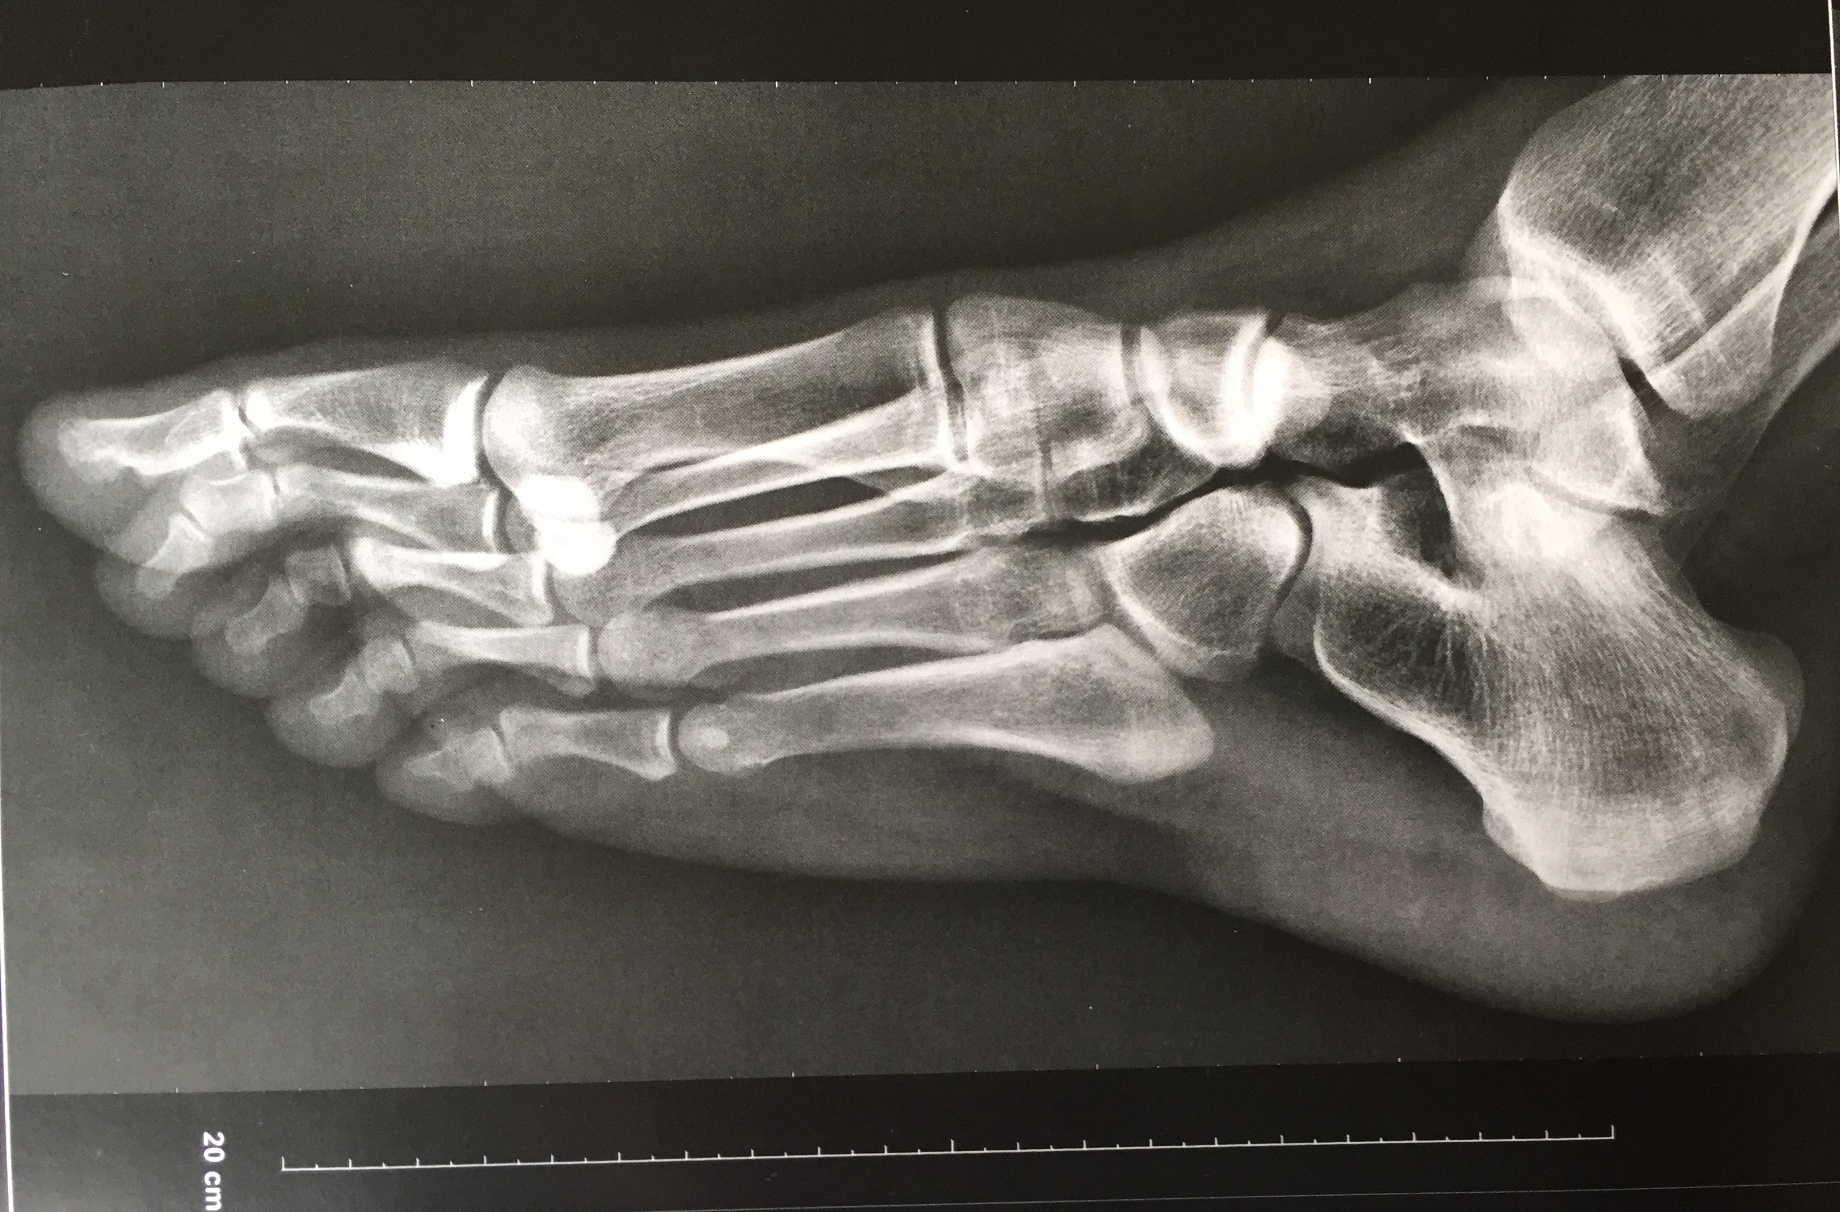

Le pied et la cheville

Le pied et la cheville peuvent être sources de nombreuses pathologies ou blessures, tant chez les sportifs que les non sportifs. Ces blessures empêchent la reprise des activités, tant sportives que professionnelles, source d'impatience et d'anxiété.